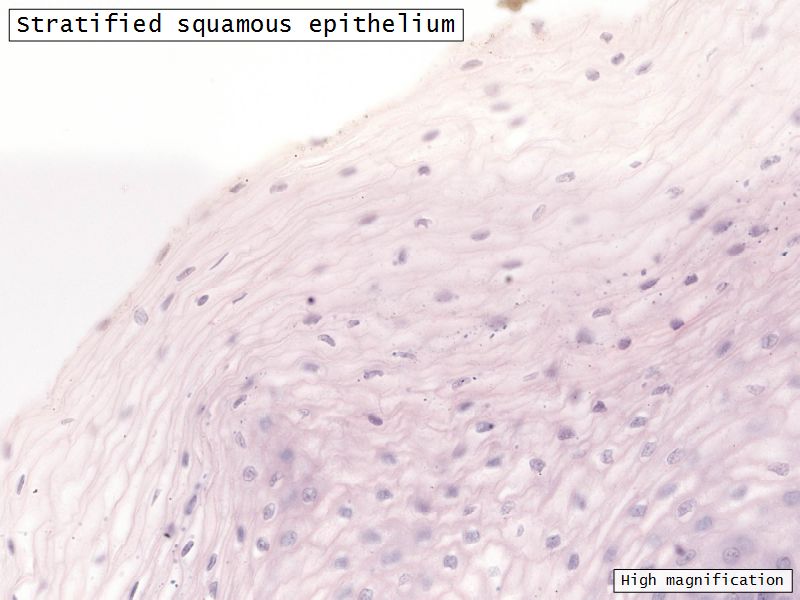

Mucosa

- Epithelium

- Thick stratified squamous nonkeratinized